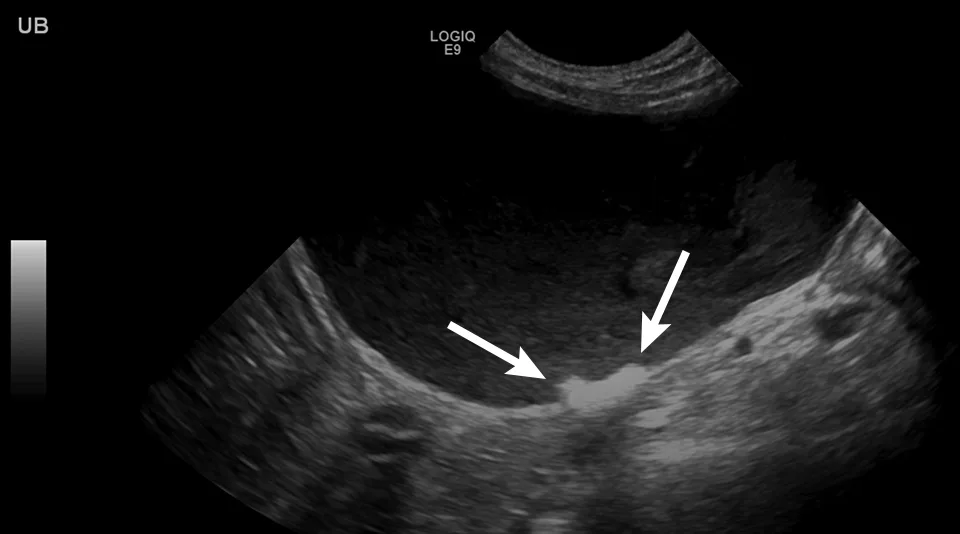

Urinary calculi are hyperechoic to the urine and can cast a distal acoustic shadow (ie, black streak under each calculus), regardless of the composition. In the author’s experience, increased power of the ultrasonography beam and advanced ultrasonography technology designed to minimize shadowing allow calculi to be at least 3 mm prior to creating a shadow. Lack of a distal acoustic shadow on small, gravity-dependent, hyperechoic foci does not therefore exclude diagnosis of sandlike calculi, although urinary sediment can have a similar appearance and can settle with gravity. Spatial resolution (ie, ability to distinguish 2 adjacent objects with the same echogenicity) is poor with ultrasonography, and multiple small calculi can appear as a single large calculus (Figure 4). Agitating the urinary bladder or repositioning the patient into sternal or lateral recumbency can help shift the calculi to determine the approximate length. In addition, measurements should be made parallel to the ultrasound beam for optimal accuracy; however, distal acoustic shadowing precludes these measurements. A reliable method of determining calculi type on ultrasound is not known.

Sagittal image of the urinary bladder with a collection of hyperechoic calculi (arrows) along the gravity-dependent dorsal border. Individual calculi cannot be seen due to poor spatial resolution. Echoic floating sediment, a nonspecific finding more common with higher-resolution probes, is present. Left, cranial; bottom, dorsal